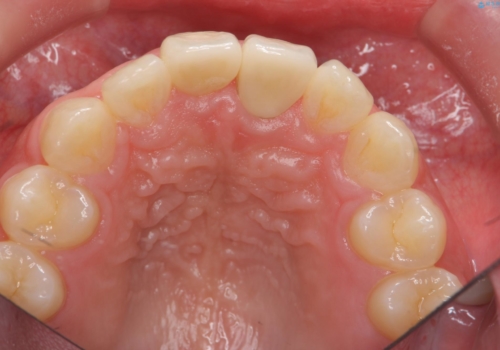

治療結果には大変満足されていました。

笑っても大きく歯ぐきが見える方ではなかったので、歯ぐきのラインが目立つことはなかったです。

手術をしなければ左上1番の歯頚ラインは左上2番よりも短い位置になっていたため、歯自体の長さが不自然なほど短くなってしまったと思います。